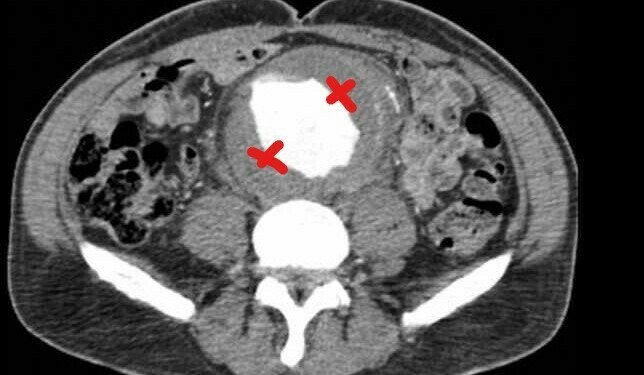

- 79 yaş erkek, trombositopenisi var, burun kanaması ve yaygın beden morluklarıyla, infrarenal abdominal aort anevrizmasından opere, geçenlerde ileus tanısı almış ve suprarenal anevrizma (8 cm) saptanmış. Anevrizması genişleyerek hastanın mortalitesini arttırmayı sürdürüyor.

- Hgb 9, plt 70, wbc 4.8. Myelodisplazi akla geliyor, kemik iliği inceleniyor ama hayır, sorun yok. Pt 17.7, aPtt 42, fibrinojen 0.7, D-Dimer yüksek saptanıyor. Kanaması artarak devam eden hastaya kırmızı hücreler, trombosit, taze donmuş plazma ve kriyopresipitat veriliyor.

- Hasta yaygın damar içi pıhtılaşma tanısı alıyor. Ayırıcı tanı için sepsis taraması ve tümör belirteçlerine bakılıyor ama hayır, yine negatif bulgular.

- Kronik damar içi pıhtılaşmanın nedeni anevrizma.

- Yapılan çalışmalar göstermiş, anevrizma duvarında sürekli bir trombosit birikimi ve fibrinolitik aktivite var, vücut bitmeyen bir kanama yapışma döngüsünde, kaynaklarını boş beleş tüketiyor, kan elemanları içten içe eriyor, plt değeri 70 olan hastanın böyle kolay kanamaması gerekiyor.

- Kanama eğilimi olan anevrizmalı hastaların kronik yaygın damar içi pıhtılaşması olabilir.